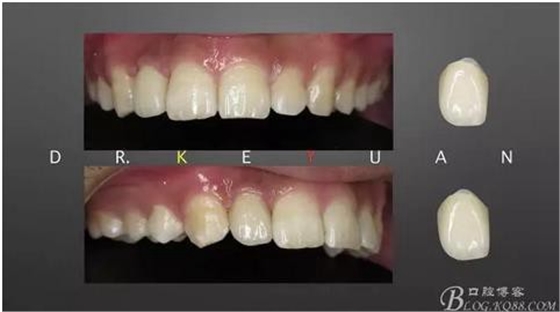

8、排齦、硅橡膠第二次取模制作氧化鋯全瓷冠

9、完成最終修復(fù)體

10、復(fù)診試戴最終修復(fù)體(又爭取了2周的時間,再加上技師對最終修復(fù)體鄰接關(guān)系的設(shè)計,牙齦恢復(fù)效果明顯)

13、術(shù)前術(shù)后對比